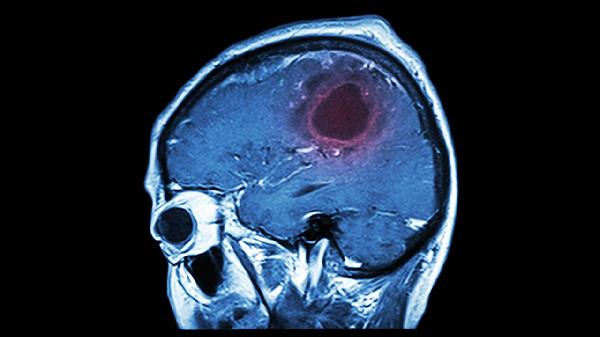

年轻人脑溢血是怎么引起的

年轻人脑溢血可能由高血压、脑血管畸形、血液病、药物滥用、不良生活习惯等原因引起,可通过控制血压、手术治疗原发病、纠正凝血功能、戒断成瘾物质、改善生活方式等方式干预。